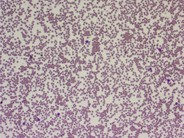

The blood film of a patient with cold agglutinin disease secondary to lymphoplasmacytic lymphoma showing red cell agglutination and two lymphoplasmacytoid lymphocytes.